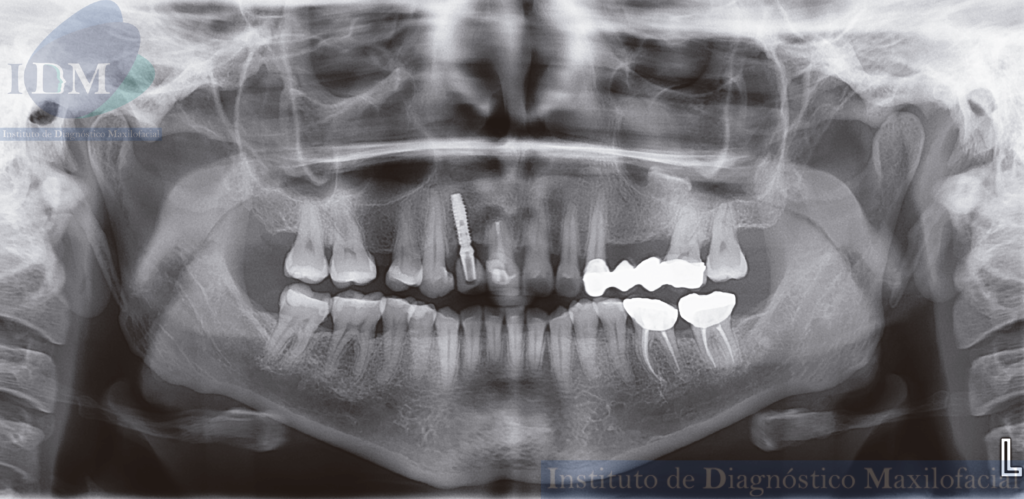

En la radiografía panorámica se observa una radiopacidad irregular en piso del seno maxilar izquierdo que se extiende desde la cortical ósea del piso hacia el antro sinusal a nivel de la zona de pieza 25 y 26.

Radiografia Panorámica